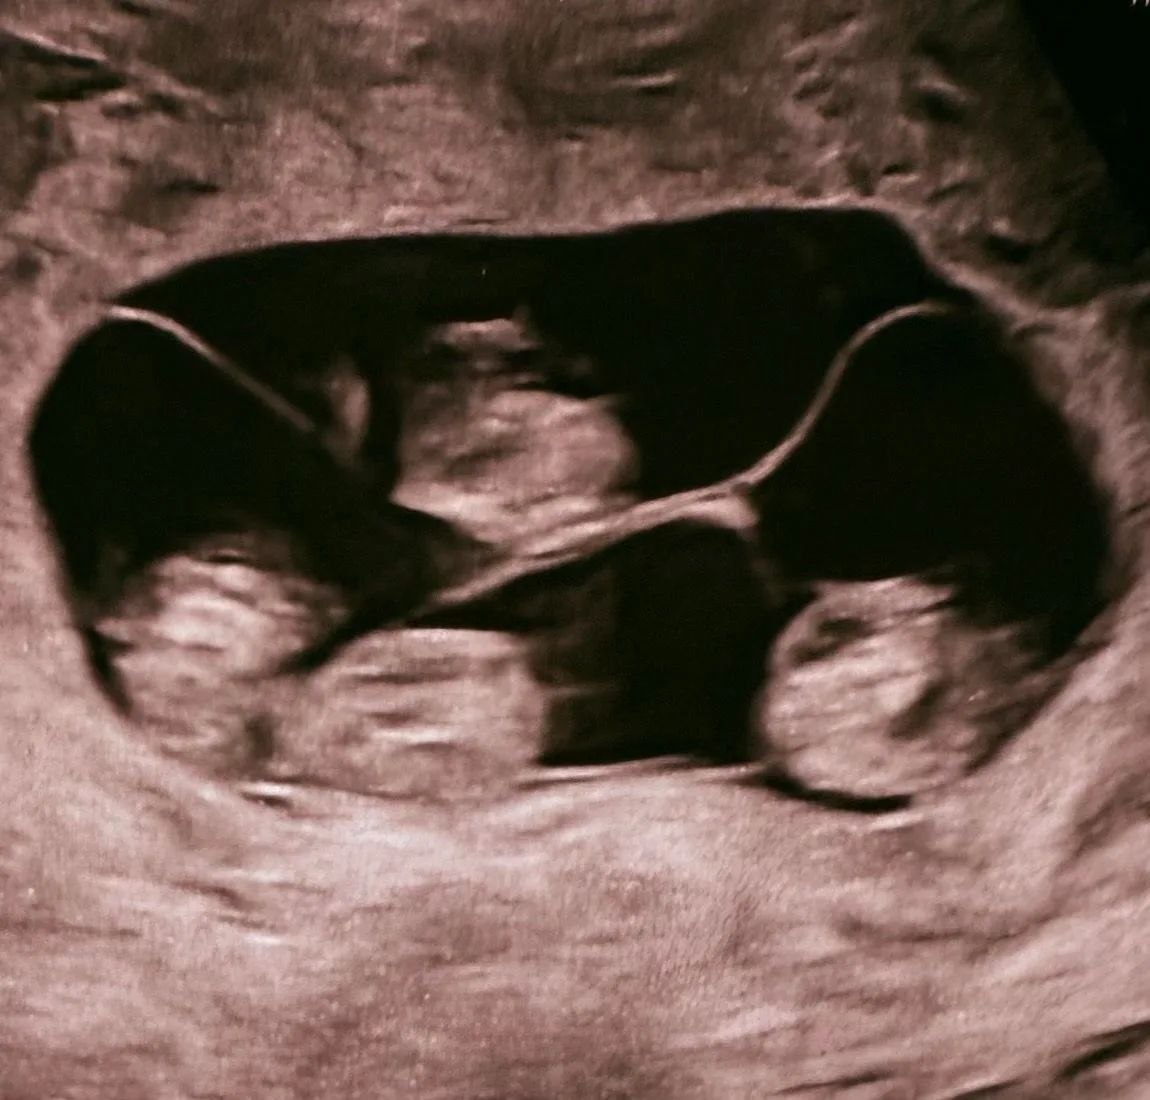

2 апреля в роддоме № 17 в Санкт-Петербурге родилась четверня: на сроке 32 недели на свет появились четыре сестренки.

Об удивительном случае не только в истории медицины, но и России, рассказали в соцсетях роддома.

«В истории нашего родильного дома была написана удивительная и редкая глава. В медицине рождение четверни — это всегда событие экстра-класса, требующее ювелирной точности, колоссальной выдержки и слаженной работы огромной команды. И это чудо произошло!», — поделились в сообщении.